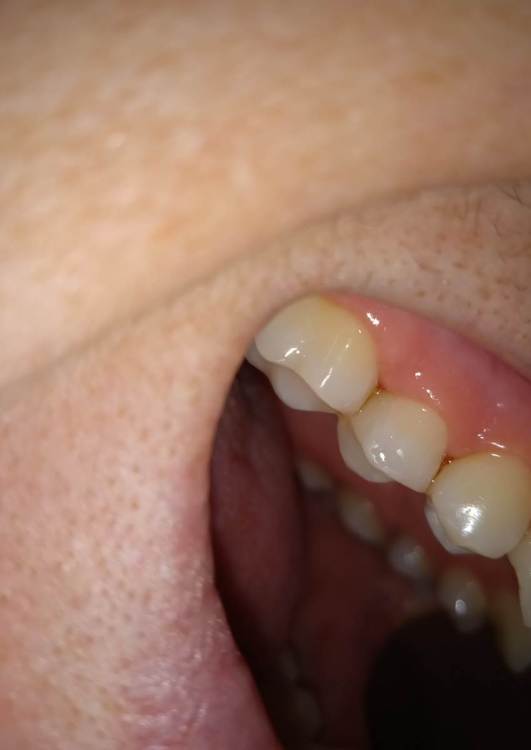

Александра117 Опубликовано 19 ноября, 2022 Поделиться Опубликовано 19 ноября, 2022 Всем Привет! Месяц назад лечила зуб верхнюю 5ку. Депульпировали и Пломбировали каналы гуттаперчей. На момент лечения в зубе уже была боль. Был поставлен диагноз пульпит. Но прошел уже месяц и боль в зубе сохраняется , при этом почти точно такая же как и до лечения. Боль постоянная ноющая средней интенсивности. Я думала это первое время после лечения такая боль будет. Но месяц прошел, а боль не уходит. Немного предыстории этого зуба: Зуб этот меня вообще не беспокоил изначально. Я пришла 12.09.2022 на прием, чтобы вылечить кариес. Стоматолог рассверлил и запломбировал. Но сказал, что очень глубокий кариес был, но решил пока сохранить пульпу и наблюдать. После лечения появились боли в зубе ,но терпимые. Через две недели боли усилились. Я пришла на прием снова с этим вопросом. Врач сказал, что после лечения глубокого кариеса могут быть боли, надо ещё понаблюдать. Ещё через пару неделю боль не проходила. Была довольно сильной. Врач принял решение депульпировать зуб. Лечение я проходила под микроскопом у опытного эндодонтиста. Именно у него я уже до этого лечила каналы у нескольких других зубов, и все было нормально. Но также это в в первый раз такое случилось, что боли такие сохраняются в течение месяца после лечения. После лечения врач сказал, что зуб меня беспокоить не должен больше. Сказал, что было лечение неосложненного пульпита. Но он беспокоит вот уже месяц. Вообще это у меня впервые, чтобы была боль в зубе и на момент лечения и после лечения каналов. До этого до болей в зубе дело не доходило. Пролечивалось раньше. Сделала свежие снимки Рентен через месяц после Лечения, их прилагаю сюда. По снимку видно, что каналы пройдены полностью до конца. Материал за Пределы Корня не выведен. Найдены все каналы. Их у меня в верхних пятерках их по два. Как и видно по КТ. Скажите, что это может быть? И что Можно сделать? Требует ли эта ситуация какого то срочного вмешательства или можно ещё наблюдать? Может ли это быть периодонтит, при том что на снимке в прикорневых тканях все спокойно? Ещё на внешней стороне зуба есть две белые трещины. Как раз на границе пломбы и стенки Зуба. В этом месте если трогать языком очень шершавая поверхность. Также, можете сказать, эти трещины это трещины Эмали или может быть что и более глубокие Трещины? ( Фото трещин тоже прилагаю) Ссылка на комментарий